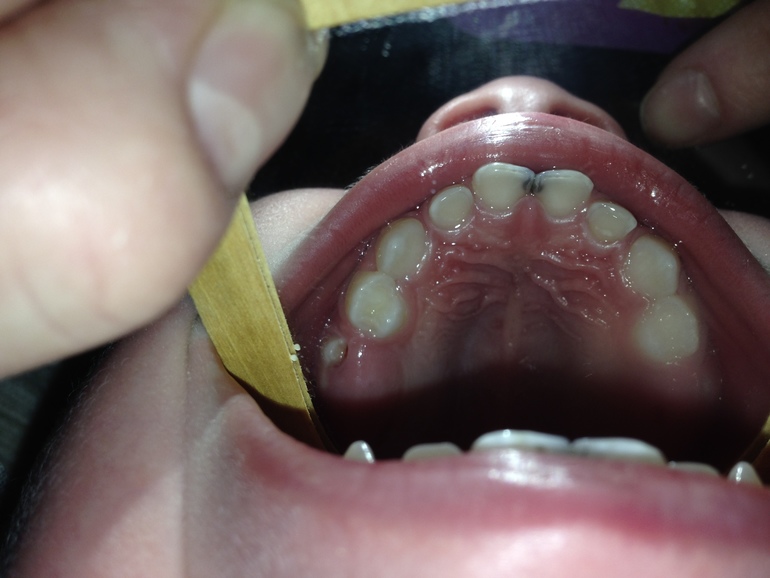

Алина, добрый вечер! вот фото с зеркалом, к сожалению это лучшее, что смогли сделать. низ изнутри так и не получился((( что касается изменения, вроде нет, хотя небольшое белое пятнышко наводит на мысль, что начинается еще один кариес(. и еще вопрос по фото - у него режутся последние жевательные, есть красное пятно - это не критично надеюсь? сосудик?  Заранее спасибо!!bbba34ed4545b4babe524b26b7a1abb6.jpgcff76e37a1eaac15884b45cf51e3561e.jpg925d9a5b0347a9820ea13ab19fb0c327.jpg7fd2df8acd6ded7a86d3a952b0d3c1d2.jpg

Здравствуйте.А на внутренней поверхности есть изменения? Сможете сделать фото через зеркало. чтобы была видна внутренняя поверхность?